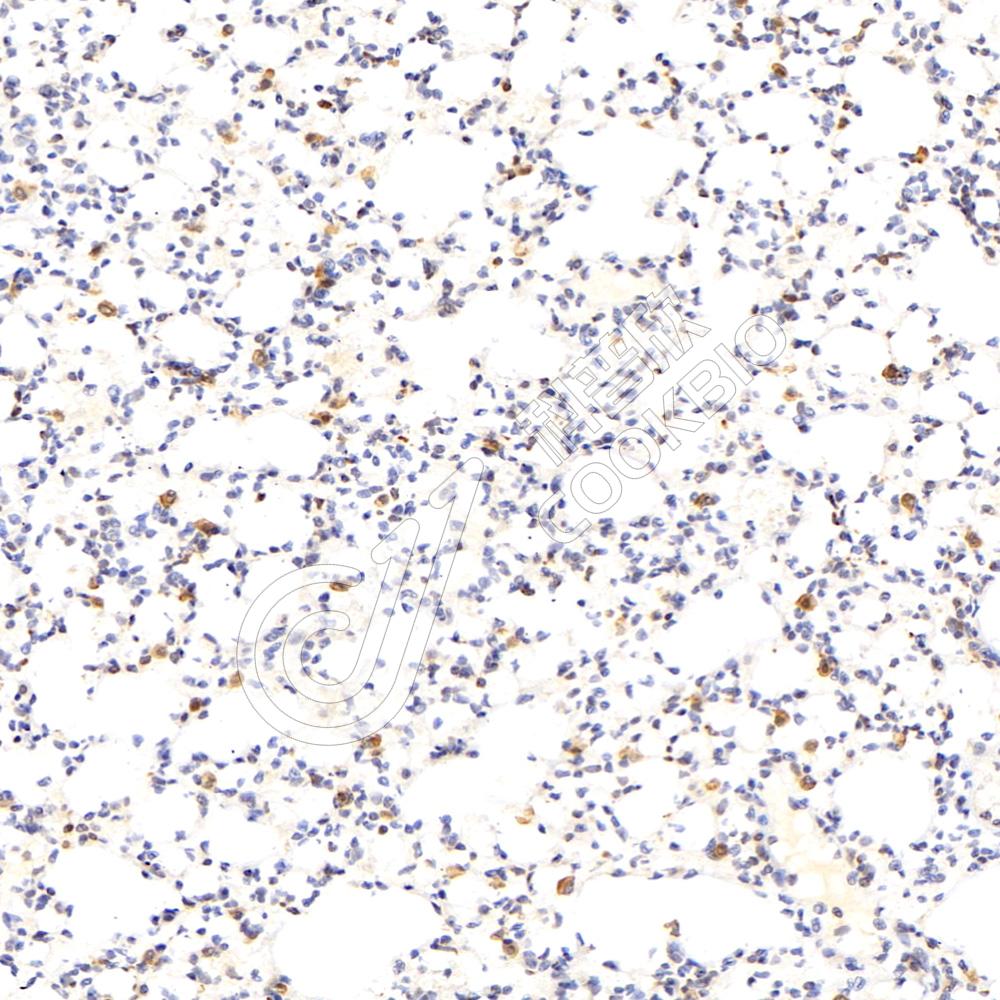

IHC检测160 kDa Neurofilament Medium蛋白(货号 K547289).

样品: 小鼠脑, 4%多聚甲醛 (货号KSG1101) 固定12-24小时.

抗原修复: Tris-EDTA抗原修复液(pH 9.0) (KSG1203), 98℃, 20分钟.

—抗: 1: 800稀释, 4℃ 孵育过夜.

二抗: S-vision免疫组化多聚二抗(山羊抗小鼠), 即用型(货号KB3903), 室温孵育20分钟.